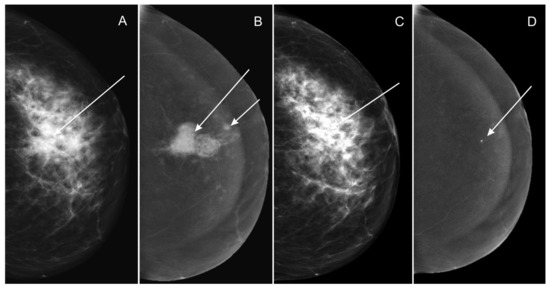

- Low-energy images from two consecutive contrast-enhanced spectral mammograms (taken before the start and at completion of neoadjuvant chemotherapy);

- Subtraction images from two consecutive contrast-enhanced spectral mammograms (taken before the start and at completion of neoadjuvant chemotherapy).